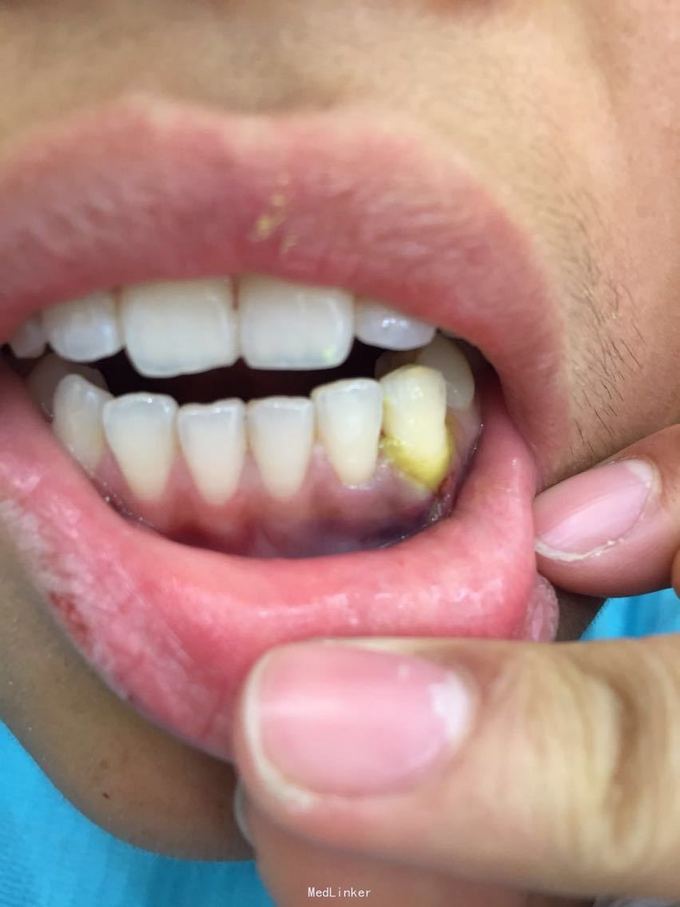

牙脱位24小时要求处理 昨晚8点吃铁板烧的时候咬到硬物致左下尖牙脱落到铁板烧中污染,取出牙齿用纸巾保存,第二天到就近医院处理,医生建议其做种植牙修复或烤瓷桥修复,脱落牙齿无法保留,患者又陆续问了4家医院都无法保留脱落牙齿,晚上8点找到我院(夜班8点下班)要求处理。

D3完全脱位,伤口血凝块已经凝固,颊侧牙龈钝性撕裂。D2D4无叩痛和松动。脱落牙齿牙体硬组织完好,牙周膜干裂,牙体上有纸屑和食物残渣,根尖有牙髓组织呈黑红色。